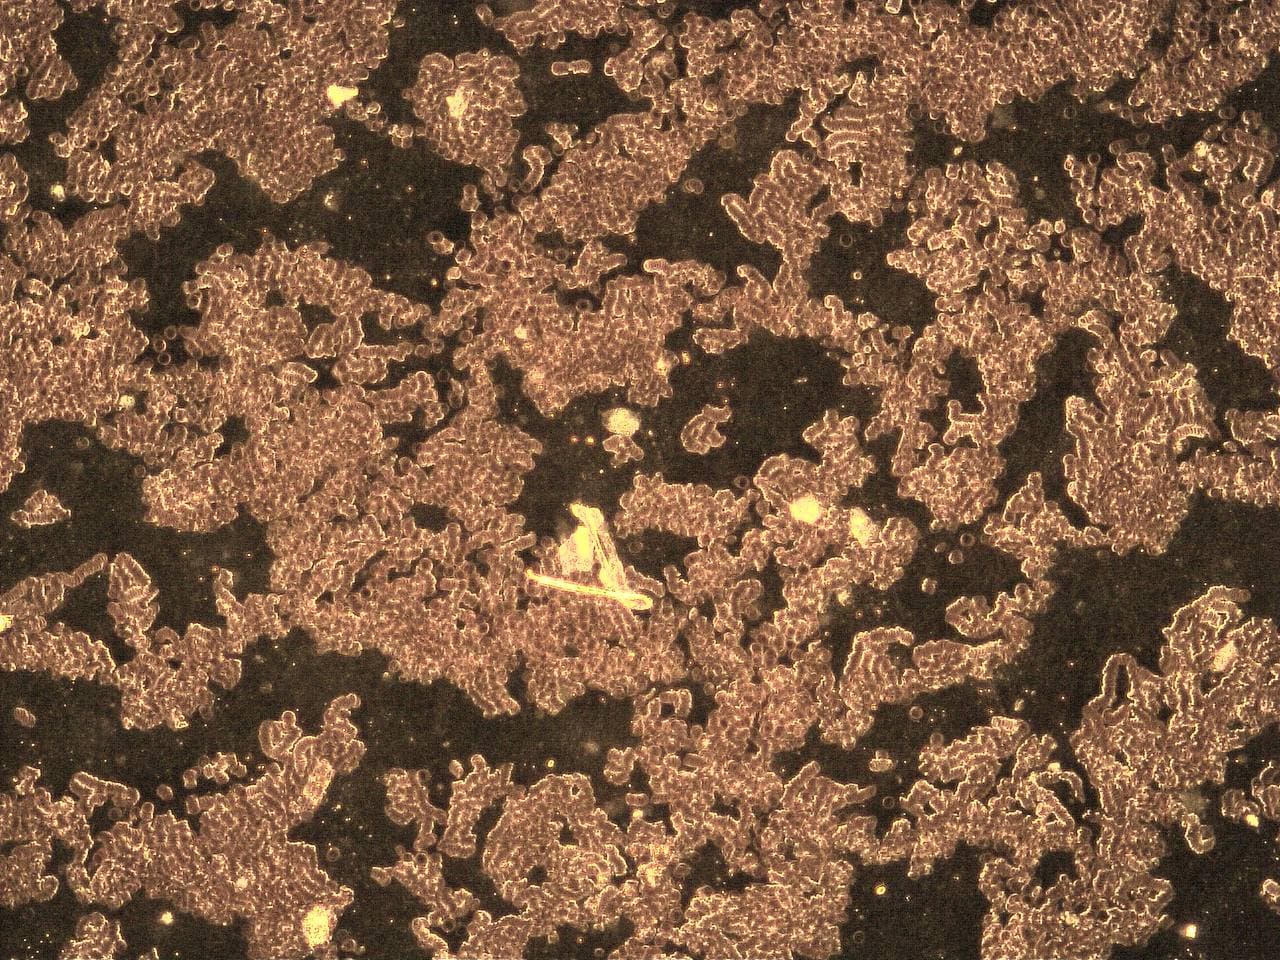

GENimpfschaden Blut nach GENimpfung Schweiz

6.11.2021: Verklebte Blutkörperchen und Gegenstände im

Blut

Impfschäden Schweiz Coronaimpfung, [06/11/2021 03:17 P.M.]

https://t.me/Impfschaden_Corona_Schweiz/28793

Diese Dunkelfeld-Bilder wurden am 28.09.2021 vom Blut eines

18 jährigen Mannes aufgenommen, der 10 Tage zuvor die erste

Dosis mit Biontech/Pfizer bekommen hatte. Sie zeigen

Anomalien, die die Untersuchende (Name ist Kanalbetreiberin

bekannt) laut ihrer Aussage in ihrer langen Zeit der Praxis

noch nie zuvor gesehen hat. Auch derjenige, der die Bilder

direkt vom Bildschirm abfotografiert hat, ist pers. bekannt.

GENimpfschaden: Blut

kaputt nach GENimpfung 6.11.2021: Die roten

Blutkiörperchen sind "gestapelt"

Impfschäden Schweiz Coronaimpfung, [06/11/2021 04:25 P.M.]

https://t.me/Impfschaden_Corona_Schweiz/28815

[Antwort auf Impfschäden Schweiz Coronaimpfung]

Eine Meldung dazu:

Liebe Mara, das Blutbild diesen 18jährigen ist wohl der

blanke Horror. Aber postet doch bitte ein gleiches

Blutbild eines gesunden Blutes…das dürfte das Ganze noch

eindrücklicher machen….diese Bilder könnten wir dann

weiter streuen eventuell ausdrucken und in altbewährter

Papierform in die Briefkästen verteilen.

Impfschäden Schweiz Coronaimpfung, [06/11/2021 04:30 P.M.]

https://t.me/Impfschaden_Corona_Schweiz/28819

Blut kaputt nach GENimpfung 6.11.2021: Die roten

Blutkiörperchen sind "gestapelt" [19]

Impfschäden Schweiz Coronaimpfung, [06/11/2021 04:30 P.M.]

https://t.me/Impfschaden_Corona_Schweiz/28820

Blut kaputt nach GENimpfung 6.11.2021: Die roten

Blutkörperchen sind "gestapelt" [20]

Medizinisches: